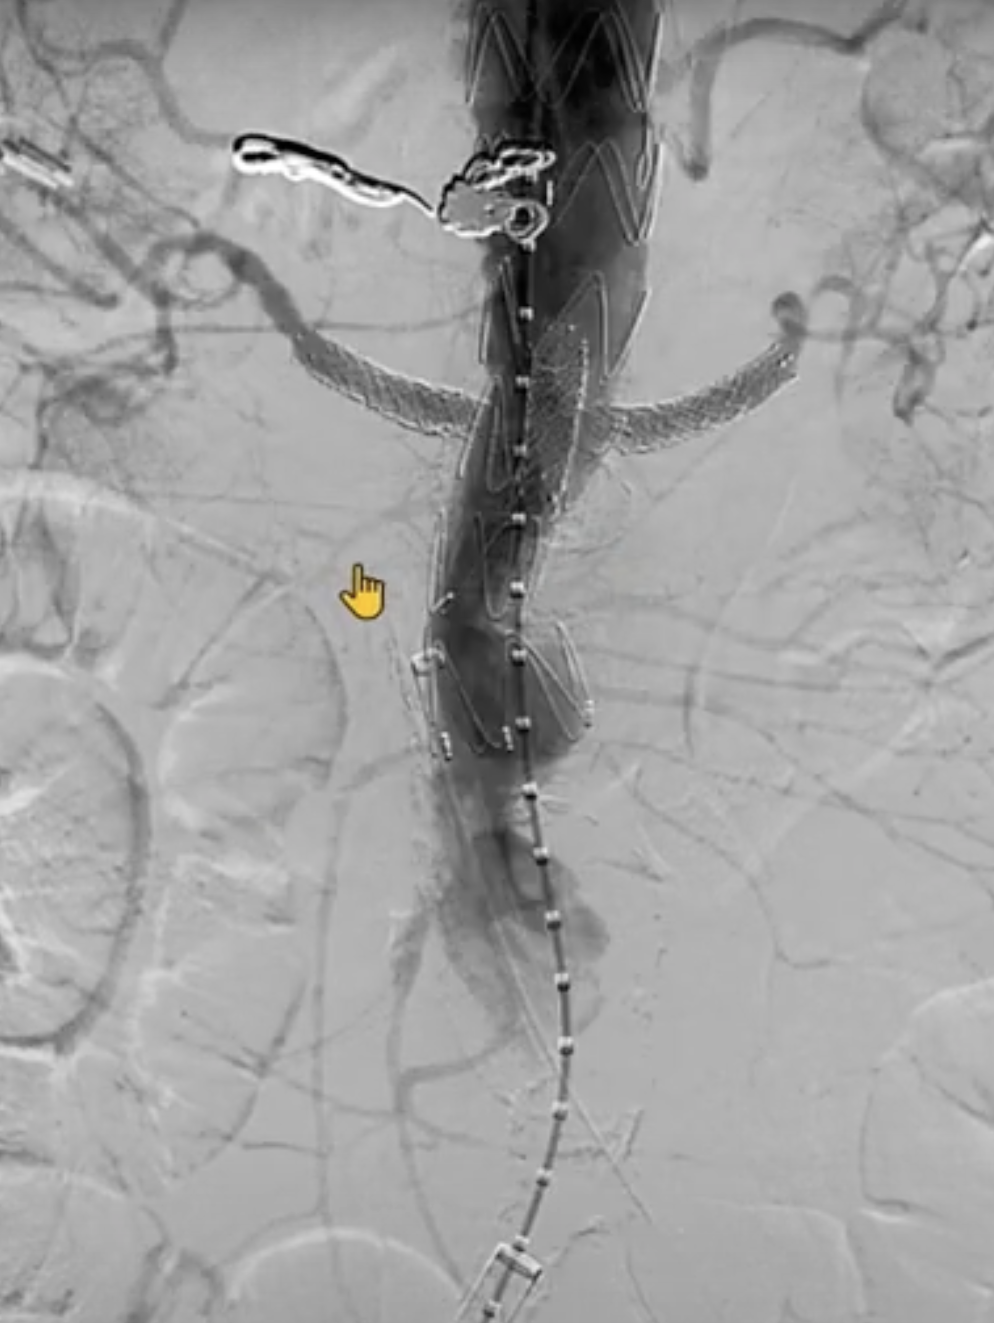

最后进行内脏动脉部分主动脉造影。注意在肾下有足够的空间(约5cm)以植入后续支架。使用普通EVAR支架完成后续的工作。

最后的正/侧位造影显示瘤腔隔绝满意,支架形态良好,主髂动脉及内脏分支动脉血流通畅。术中内脏动脉的总缺血时间<60min,肠系膜上动脉通畅在10-15min以内。

术后即刻造影